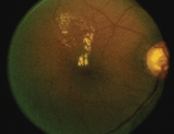

![]() 视网膜出血丶棉絮状白点及渗出物 |

糖尿上眼早期并没有症状,眼睛不红不痛,视力亦正常。然而,若病情没有受到控制,视网膜上的微丝血管会逐渐膨胀,出现微小血管瘤,渗漏出血清和血脂,部份微丝血管更会闭塞并导致缺氧。如果病情不受控制,或患者根本不知道自己糖尿上眼,眼睛会长出新生血管,它们相当脆弱,很容易突然爆裂,导致血块渗入眼球中的玻璃体。患者的眼睛会因此出现大量飞蚊,随後视力会下降,严重者甚至突然完全失明。